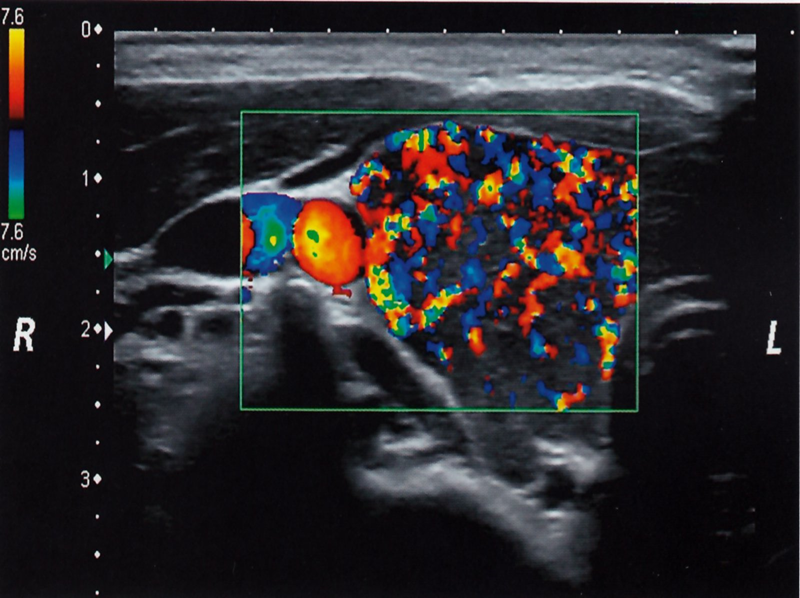

Thyroid ultrasound (with color Doppler) Shows an enlarged, hypervascular thyroid

Thyroid ultrasound of the right thyroid lobe (color Doppler) Numerous red and blue areas consistent with increased vascularization are visible within the color Doppler image window (green rectangle).

This finding is typical in Graves disease.